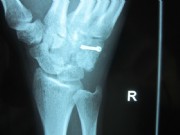

Fracture of the hamate bone

The young man (boxer) punched aggressively and once felt a sharp pain in the wrist.

After fitting and a 6 weeks cast, the patient was able to start training again.